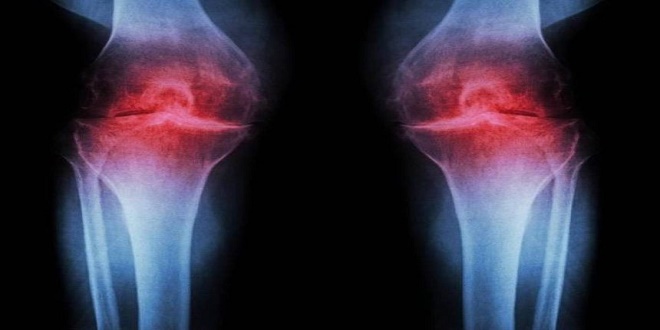

علاج جديد يعيد بناء غضروف المفاصل

وأظهرت الدراسة، التي أجريت على الفئران أن فقدان الغضروف مع التقدم في العمر يرتبط بزيادة نشاط بروتين يُعرف باسم “15-PGDH”، الذي يقلل قدرة الجسم على ترميم الأنسجة وتقليل الالتهاب، وعند تثبيط هذا البروتين لدى الفئران المسنة، لوحظت زيادة سماكة غضروف الركبة المحلّل، وحماية الفئران الصغيرة من تطور الفُصال العظمي بعد إصابات مفصلية، ما يشير إلى قدرة الغضروف نفسه على التجدد دون الاعتماد على الخلايا الجذعية.

كما اختُبر العلاج على عينات غضروفية بشرية، حيث ظهرت زيادة صلابة الغضروف وتراجع مؤشرات الالتهاب، مع تحسن الحركة وحمل الوزن لدى الفئران المعالجة، وهو مؤشر غير مباشر على تقليل الألم وتحسين الوظيفة الحركية.